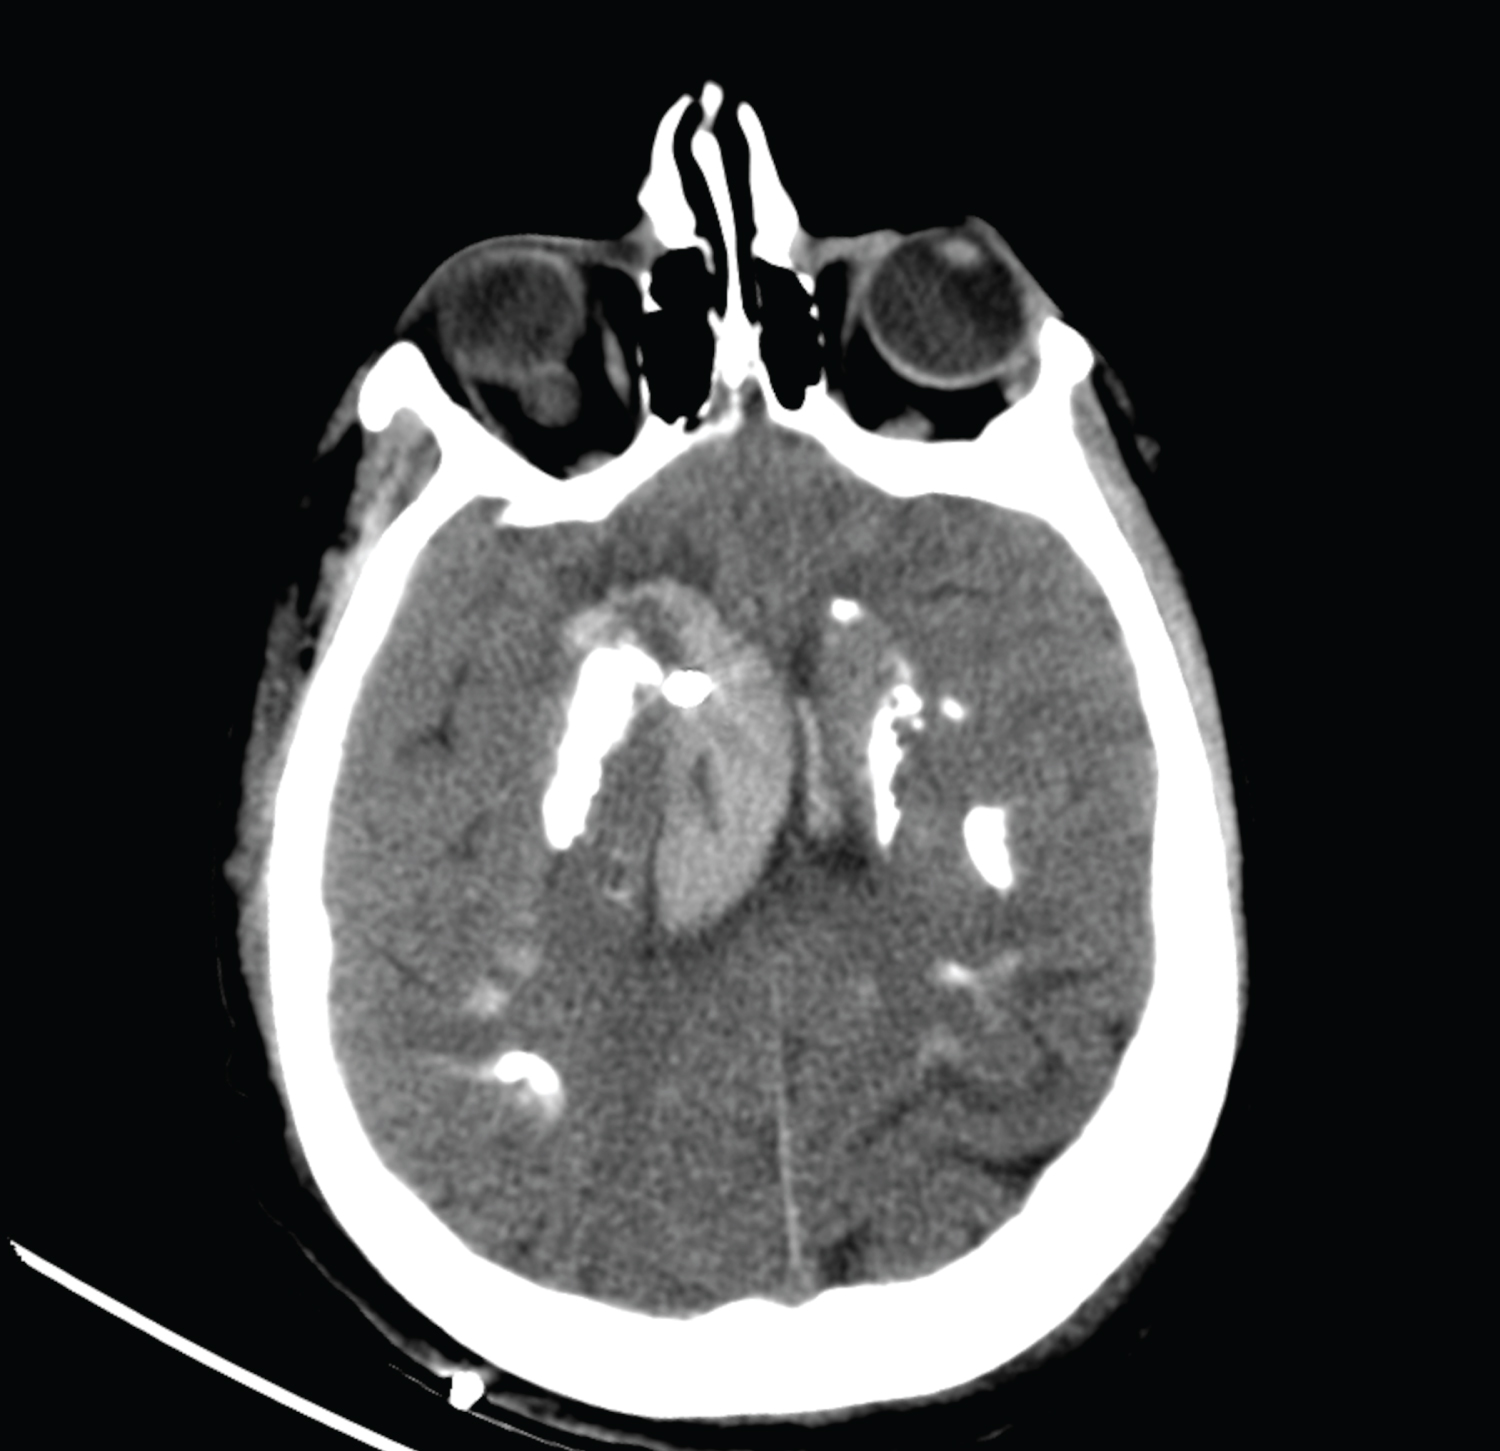

27-year-old female patient who was brought to the Emergency Department of our hospital with the complaints of severe headache and vomiting. Her general condition was moderate, she was conscious, disorientated, and cooperative. Pupils were isochoric, bilateral light reflex was positive, and there was no lateralized motor deficit. Glasgow Coma Score was evaluated as 14 points. Blood pressure was measured to be 130/80 mmHg, pulse was 90/min, respiratory rate was 14/min, and fever measured 36 centigrade degrees. Head CT reported as hyperdense appearance compatible with intraventricular hematoma in both lateral ventricles and at the level of 3rd and 4th ventricle (Figure 1). Disseminated subarachnoid hemorrhage and additionally widespread calcification across bilateral basal ganglia, thalamus, and subcorticalwhite matter detected. Patient first taken to the OR to place an external ventricular drainage (EVD) catheter (Figure 2). Then DSA performed which revealed saccular aneurysmatic filling with 5*3 millimeters in diameter at the apex of the right Internal Carotid Artery just before theM1 segment of Middle Cerebral Artery. Endovascular coil placement was performed for aneurysm treatment (Figure 3). Then patient was taken to the neurosurgery intensive care unit for post-operative (PO) close follow-up. On the PO-5th day, she was taken to the in-patient floor due to wellness in her general condition. Control angiography showed successful closure of the aneurysm (Figure 4). Patient followed up three days with EVD closed as the clarification of the color of the cerebrospinal fluid in the catheter and resorption of the intraventricular hemorrhage in the control tomography observed (Figure 5). As no changes seen in the clinical status EVD catheter removed and patient discharged to home on the PO-12th day.

Figure 5: Control brain tomography taken to observe the resorption of hemorrhage after clarification of the cerebrospinal fluid in the External Ventricular drainage catheter. View Figure 5